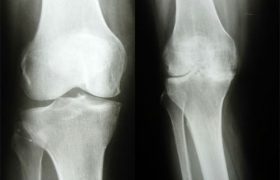

Самые распространенные заболевания опорно-двигательного аппарата — это артрозы, дегенеративные изменения суставов. Говоря проще, это изношенность суставов. Еще проще — их старение. При этом сам пациент может быть молодым, просто в силу некоторых жизненных обстоятельств его суставы преждевременно состарились.

Избыточный вес резко повышает риск развития артроза. При этом чаще всего страдают опорные суставы: коленные и тазобедренные, так как они...